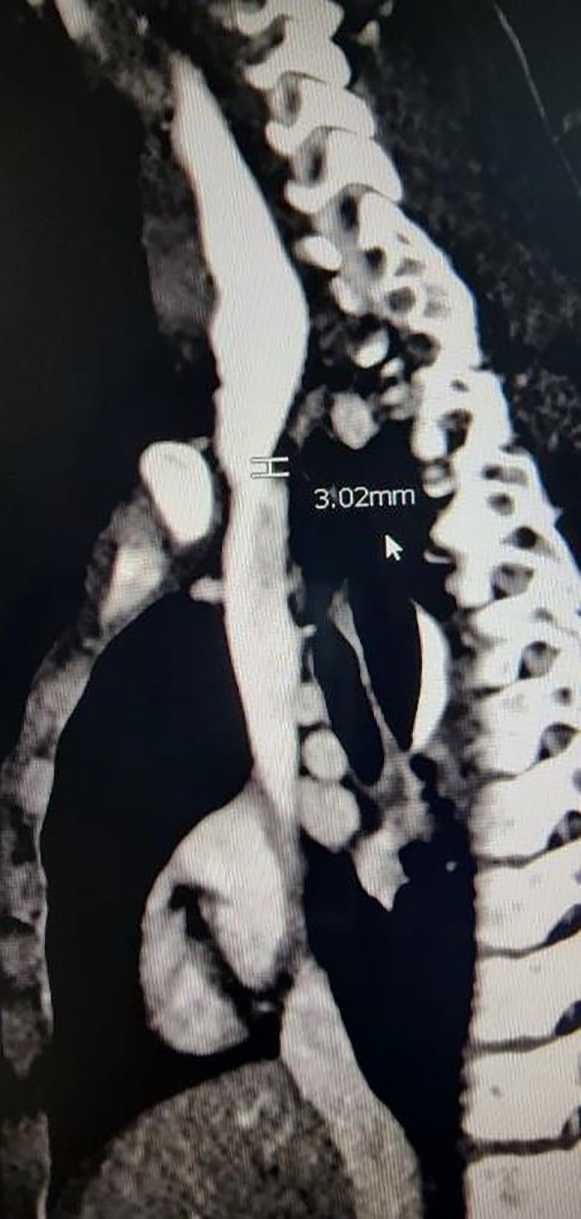

Trauma-related biliary/pancreatic injury: Fifteen EUS were done for initial evaluation of traumatic biliary (n = 8) and pancreatic (n = 7) injuries involving motor vehicle collisions, handlebar injuries, and hit-and-run. EUS facilitated precise identification of pancreatic and bile duct diameter thereby providing guidance on stent size placement.